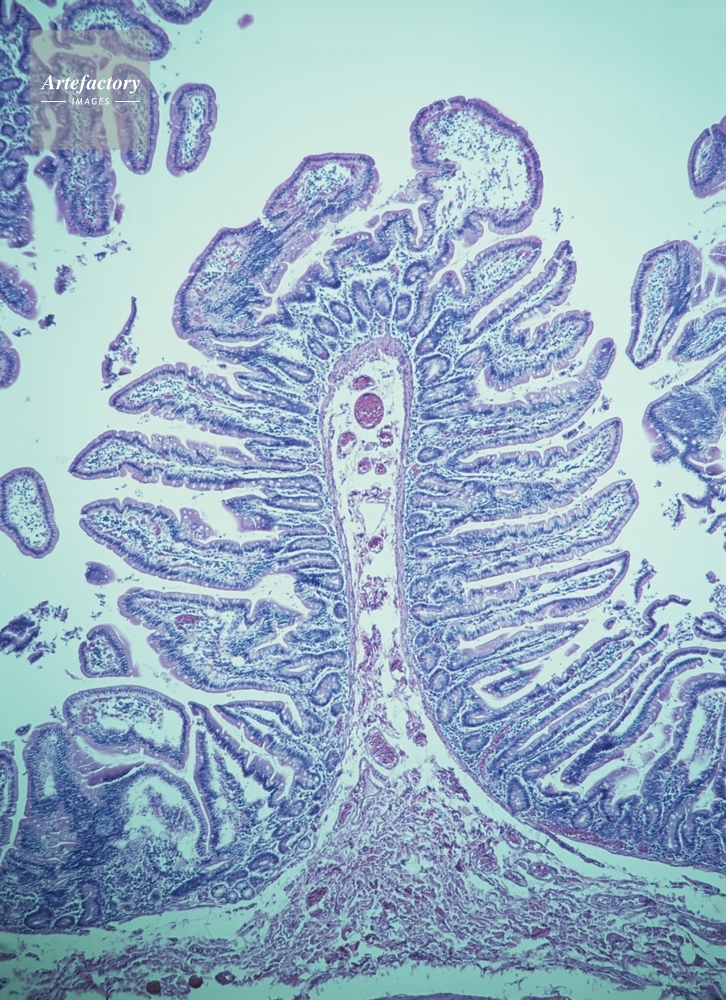

| 作品タイトル | 小腸(空腸)柔毛 | モデルリリース | なし | |

| キャプション | ヘマトキシリンエオシン。長辺55㎜の場合、顕微鏡倍率20倍 | 制限事項 | ||